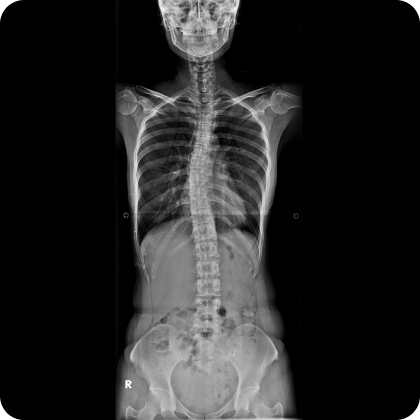

▲ 치료 전 (2016년 1월 21일)

▲ CTA 5개월 착용 (2016년 6월 29일)

▲ CTA 9개월 착용 (2016년 10월 29일)